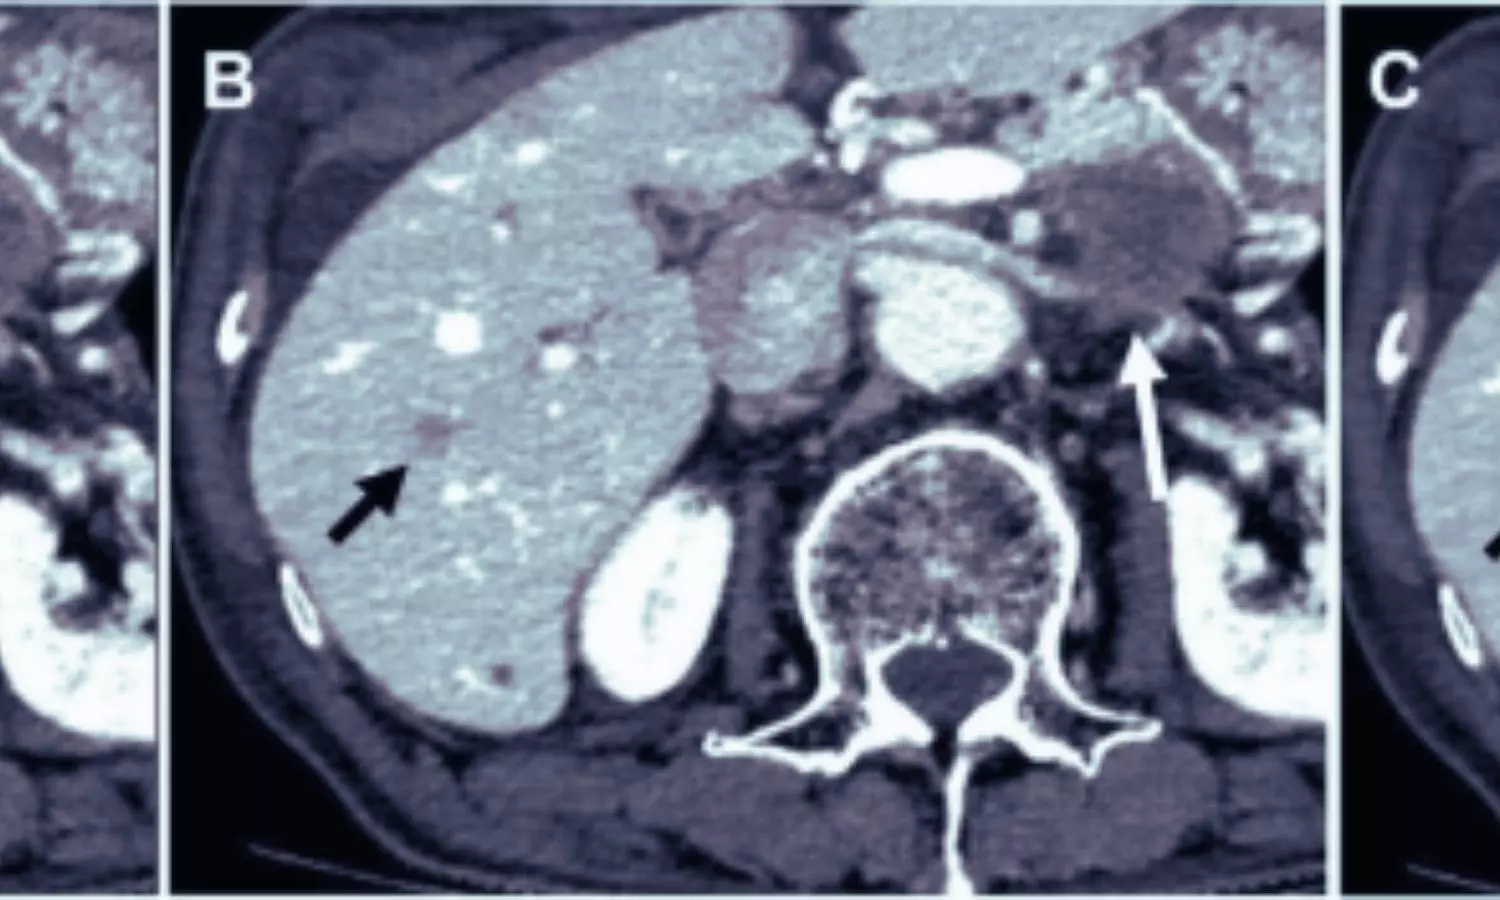

Dual-energy CT portal venography (DE-CTPV) is essential for visualizing the portal venous system and guiding preoperative planning and postoperative follow-up in hepatobiliary surgery and liver transplantation. However, efforts to reduce radiation exposure and contrast-related risks often compromise image quality. Deep learning image reconstruction (DLIR) has emerged as a potential solution, though its effectiveness in dual-low dose DE-CTPV has remained uncertain.

To address this, researchers led by Chong Meng from the Affiliated Hospital of Xuzhou Medical University, China, compared DLIR with adaptive statistical iterative reconstruction (ASIR-V) in a dual-low dose DE-CTPV setting. The study examined whether DLIR could preserve or enhance image quality across major portal venous structures despite reduced radiation and contrast use.

Images were reconstructed using DLIR at medium and high strengths and ASIR-V at 50%. Image quality was assessed across the main, left, and right portal veins, splenic vein, and superior mesenteric vein using objective measures such as image noise, contrast-to-noise ratio, and signal-to-noise ratio, alongside radiologists’ evaluations of image clarity, edge sharpness, and diagnostic confidence.

- Deep learning image reconstruction, particularly the high-strength setting, consistently outperformed ASIR-V across all evaluated vascular segments.

- DLIR-H significantly reduced image noise while achieving higher contrast-to-noise and signal-to-noise ratios.

- Improved noise reduction and signal quality enabled clearer visualization of portal venous anatomy despite lower radiation dose and reduced contrast volume.

- Radiologists gave DLIR-H the highest ratings for overall image quality, vascular edge sharpness, and diagnostic confidence.

- Use of 55 keV virtual monoenergetic imaging enhanced iodine contrast.

- DLIR effectively mitigated the increase in image noise associated with low-keV imaging, ensuring consistent and clear vascular delineation.